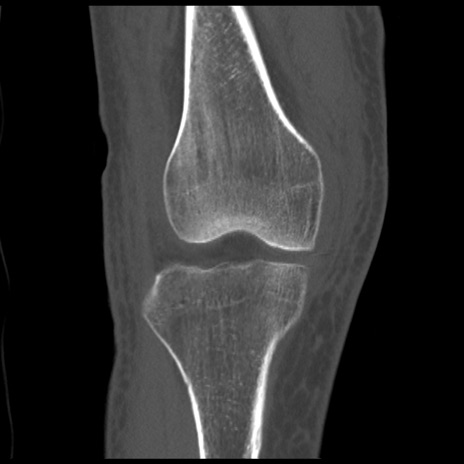

右膝関節CT

矢状断像